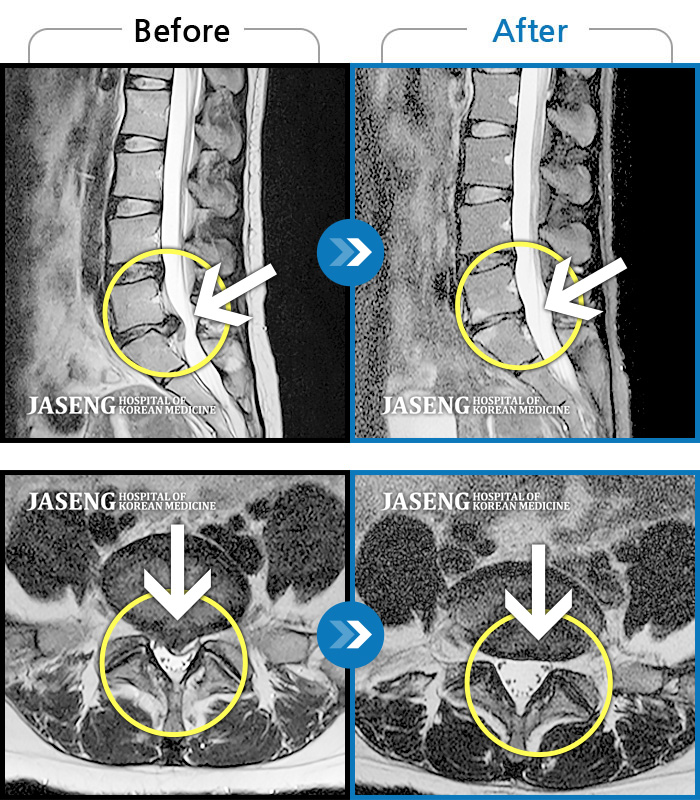

• 허리디스크